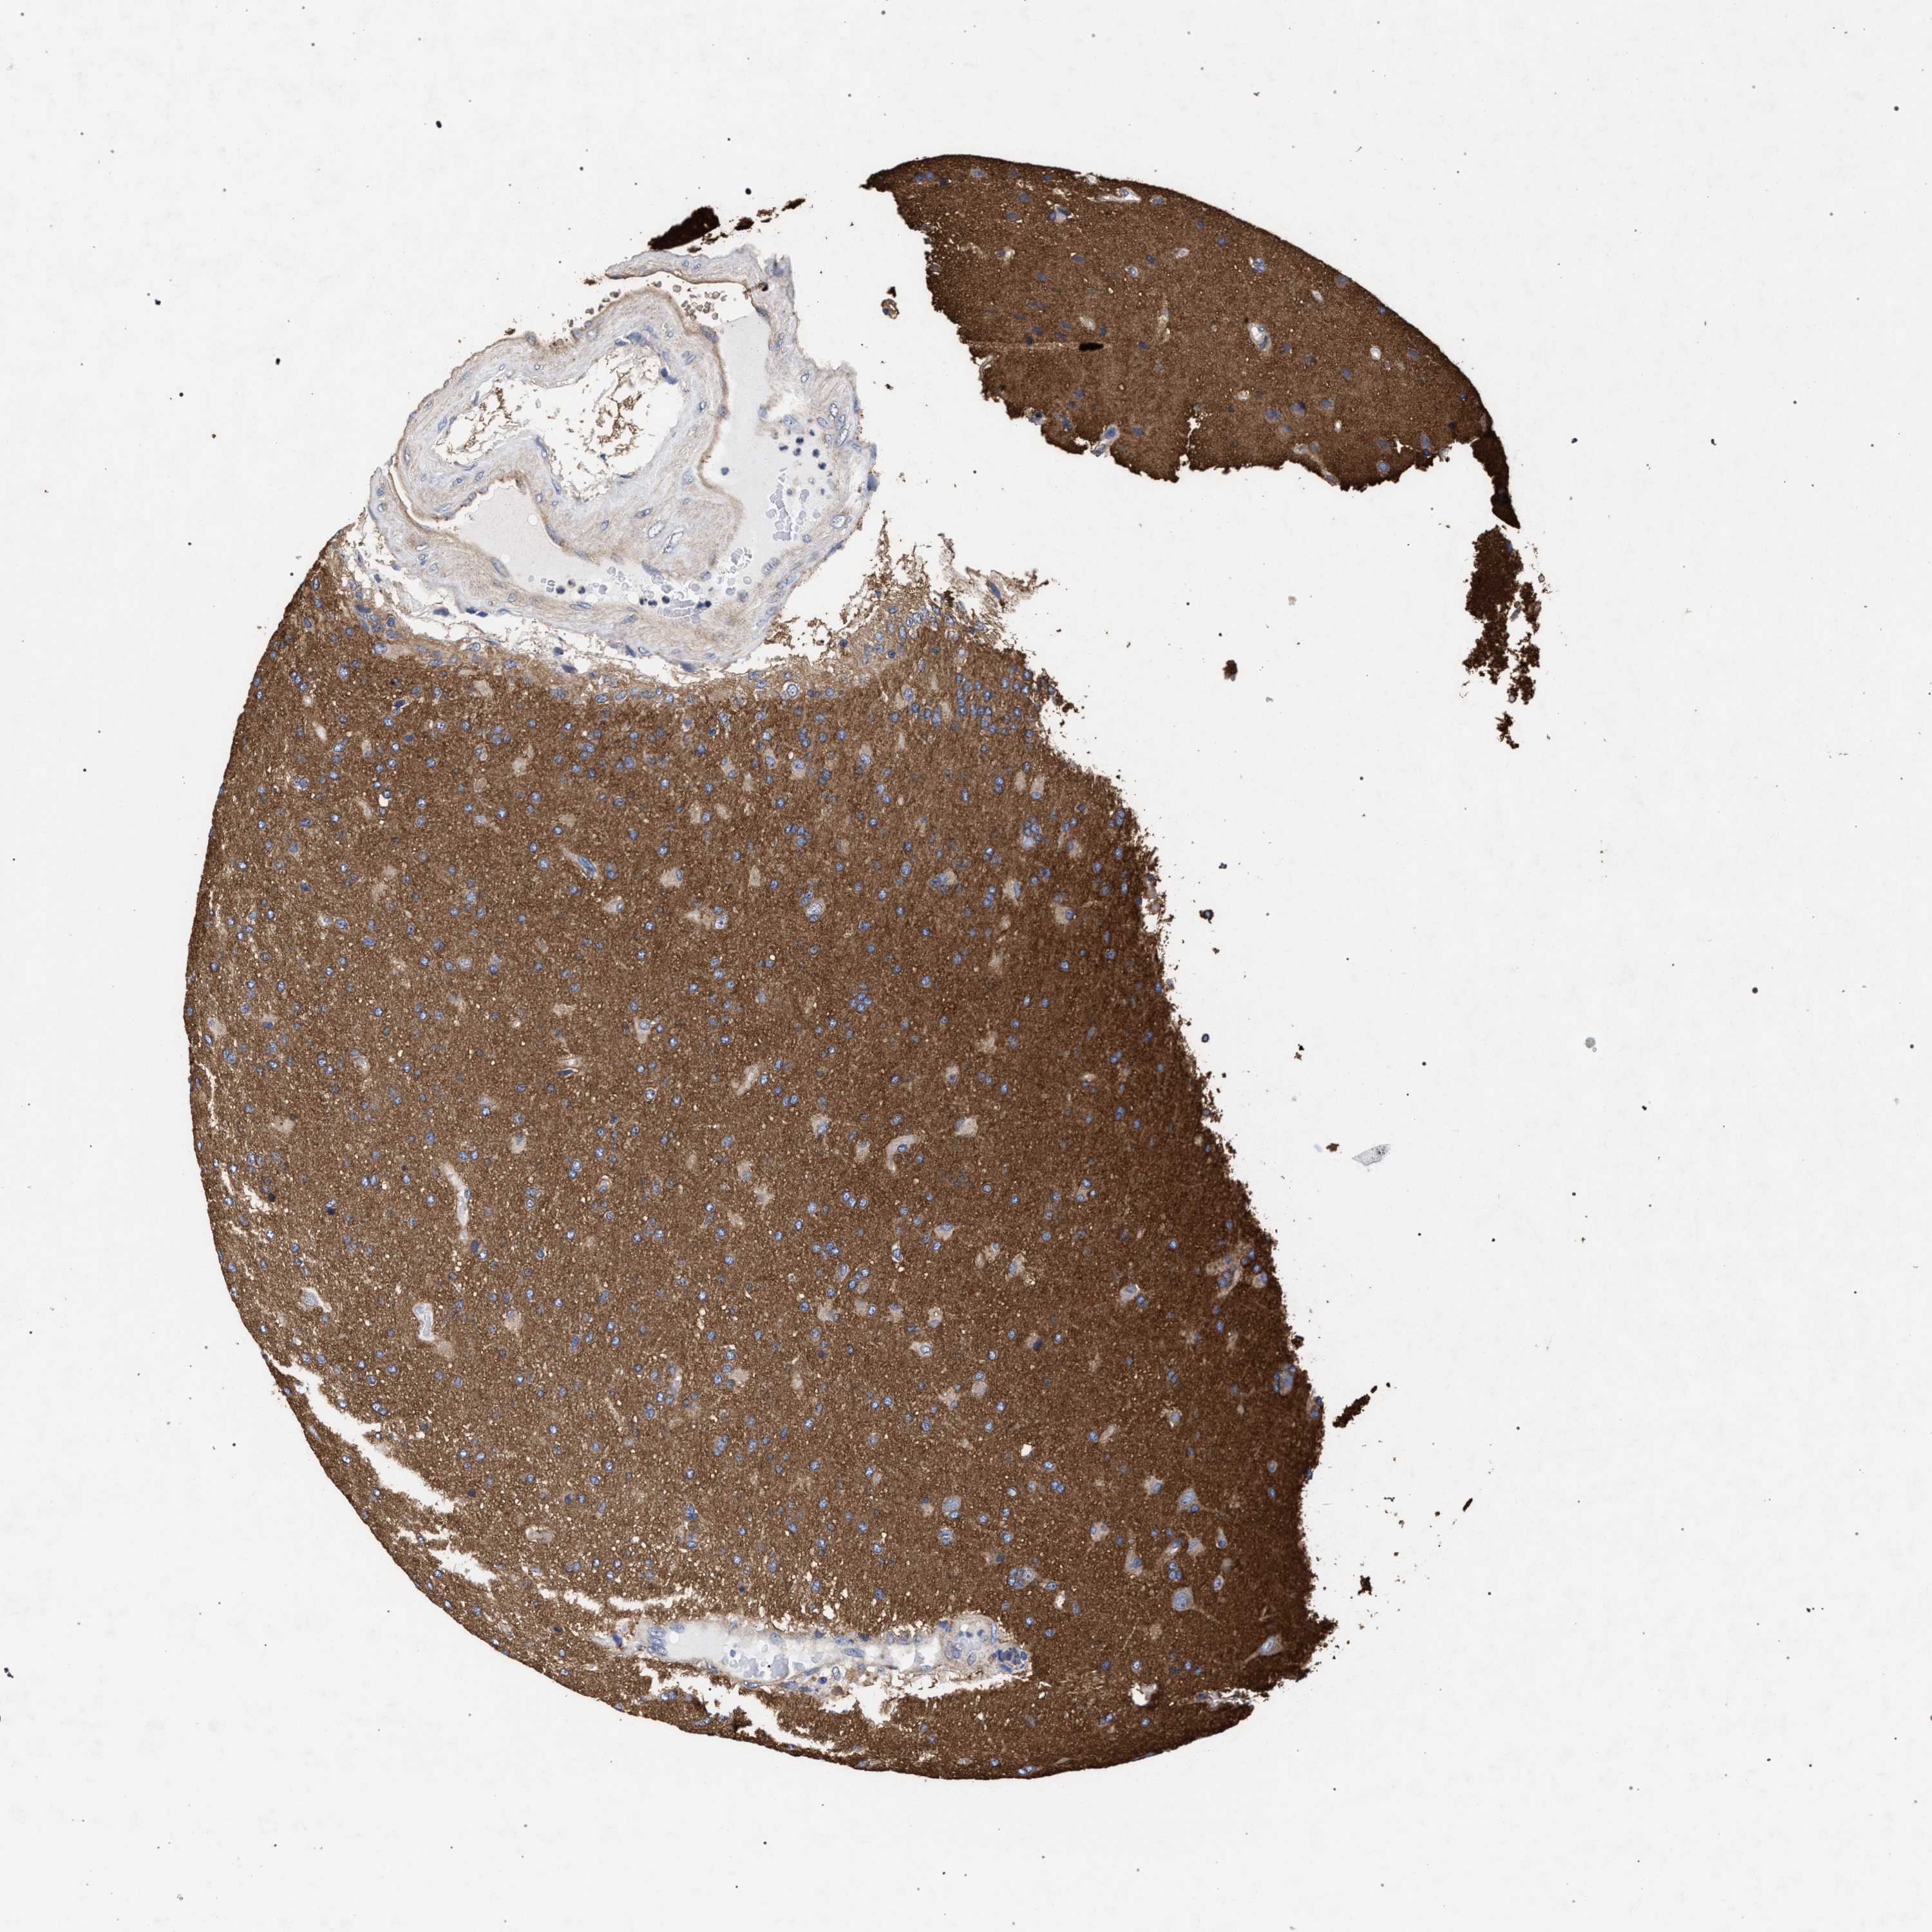

GLIOMA - Protein expressioni

A mouse-over function shows sample information and annotation data. Click on an image to view it in a full screen mode. Samples can be filtered based on level of antibody staining by selecting one or several of the following categories: high, medium, low and not detected. The assay and annotation is described here.

Antibody stainingi

Antibody staining in the annotated cell types in the current human tissue is reported as not detected, low, medium, or high, based on conventional immunohistochemistry profiling in selected tissues. This score is based on the combination of the staining intensity and fraction of stained cells.

Each image is clickable and will lead to virtual microscopy that enables deeper exploration of all samples and also displays staining intensity scores, fraction scores and subcellular localization as well as patient and tissue information for each sample.

Antibody HPA021261

Antibody HPA021325

Staining

High

Medium

Low

Not detected

Intensity

Strong

Moderate

Weak

Negative

Quantity

>75%

75%-25%

<25%

None

Location

Nuclear

Cytoplasmic/membranous

Cytoplasmic/membranous,nuclear

Glioma, malignant, High grade

Glioma, malignant, Low grade